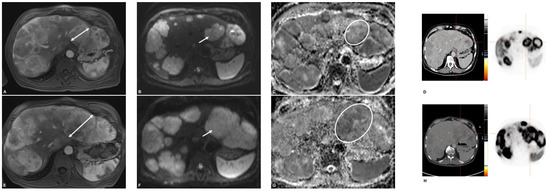

2.3. MR Imaging

2.4. PET/CT

2.5. Image Analysis